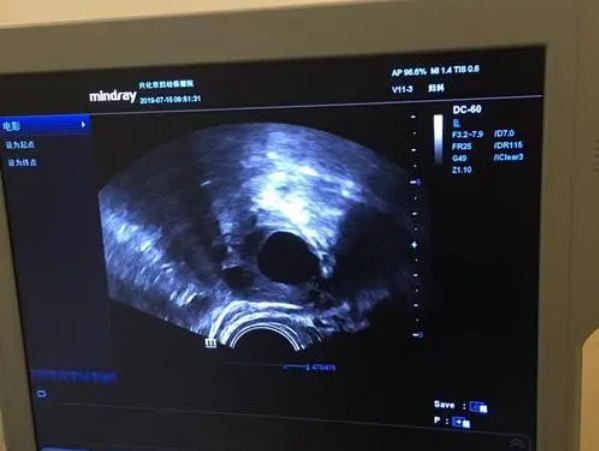

总的来说,随着女性年龄的不断上升,卵泡数量会呈现断崖式下降,所以如果有生孩子的想法,最好还是早一点备孕。如果大家想了解自己的卵泡数量,可以在月经的第5天或第6天前往医院进行检查,该时间段内的检查结果最为准确,能够比较客观的反映患者真实的卵巢情况和基础卵泡数量。